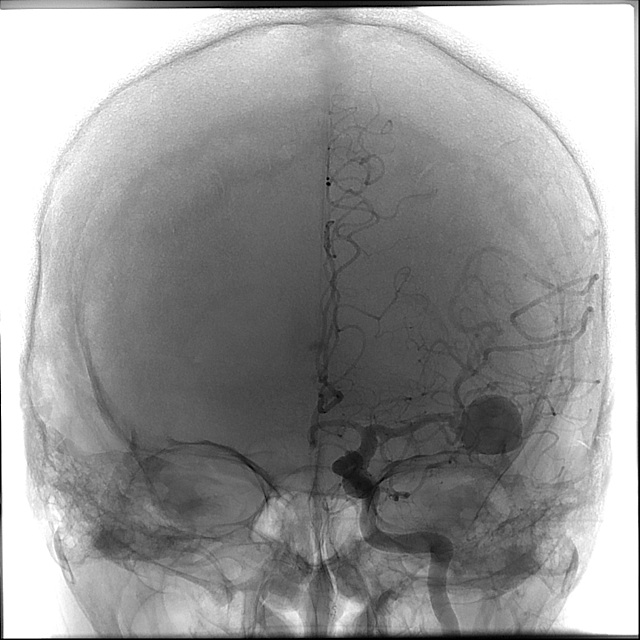

Cerebral angiography was then performed demonstrating the left MCA aneurysm. Aneurysm was measured in Image 6.

| Image 4 - Cerebral Angiogram | Image 5 - Cerebral Angiogram | Image 6 - Measurements |